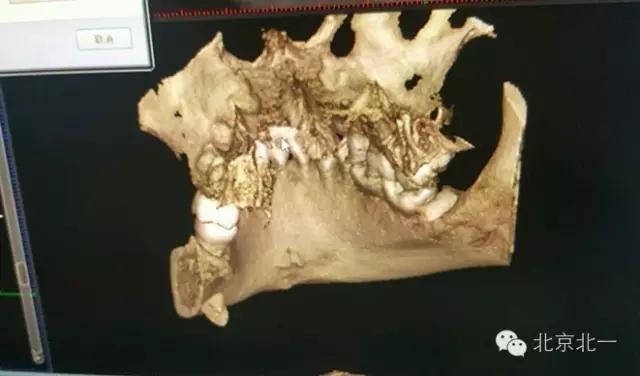

圖二:CBCT重建可見牙根位于舌側(cè)達到頜下間隙。

圖三:BCBT重建可見牙根貼在下頜骨下緣舌側(cè)面,接近頜下間隙

圖四:CBCT重建不同視覺看牙根位置